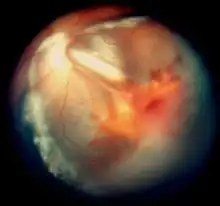

| Vitreous hemorrhage and exudative retinal detachment resembling Coats' disease in a child with cerebroretinal microangiopathy with calcifications and cysts | |

Smaller blood vessels of the retina are abnormally developed and appear tortuous and dilated to a variable extent, typically in one sector and mainly in the peripheral and temporal portions of the retina.[1][2][3][9] This is known as telangiectasia. The vessel walls are weak and leak blood plasma and lipid within and underneath the retina. This leakage can lead to exudative retinal detachment, also known as exudative retinopathy in this context. The detachment typically has a yellowish tint because the fluid under the retina contains lipid. These findings mimic Coats disease.[9] Characteristically, the abnormal vessels are localized and the retinal blood vessels peripheral to the abnormal ones seemingly have failed to develop and are thus not seen.

In some eyes, retinal vessels form small nodules on the surface of the retina, known as angiomas.[1] These can bleed and be attached to the vitreous humour. The attachment can cause traction retinal detachment.

By analogy to Coats disease, the exudative retinopathy is thought to result from breakdown of the blood-retinal barrier at the level of the vascular endothelial cell, resulting in leakage of blood plasma and lipid.[14] Macrophages then migrate into the retina and subretinal space and digest the lipid. The accumulation of the proteinaceous exudate and macrophages thickens the retina, leading to exudative retinal detachment.